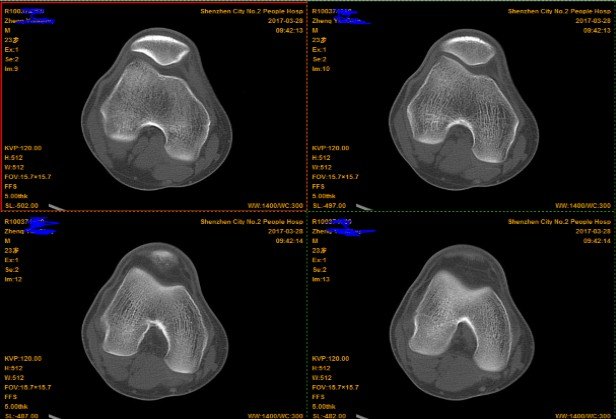

2.CT(以膝关节为例)

由于CT 是三维成像,包括矢状面,冠状面和横断面三个层面的扫描。一张CT片子也是包括医院、姓名、性别、年龄、检查日期、侧别、扫描序列等信息的。

矢状面---是从前向后、从内往外扫描成像。

冠状面---是从内向外、从前往后扫描成像。

横断面---是从上向下、从前往后扫描成像。